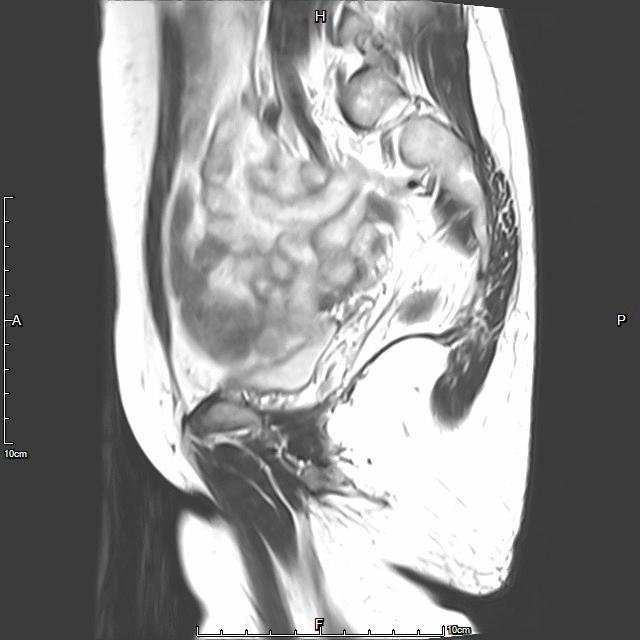

- 术前MRI显示子宫明显增大,病灶主要位于子宫前壁

术前MRI显示子宫明显增大,病灶主要位于子宫前壁

术后3个月复查MRI显示子宫明显缩小,前壁病灶萎缩坏死

- 术前MRI检查显示子宫明显增大。

术前MRI检查显示子宫明显增大